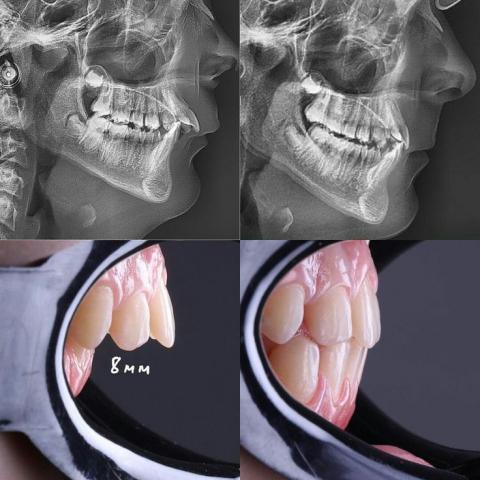

The X-ray images show a sagittal discrepancy consistent with:

A. Proclined Maxillary Incisors

The upper front teeth appear to be leaning forward, creating an 8mm anterior overjet (as labeled in the clinical photo).

This significantly affects lip support, facial profile, and function.

B. Mandibular Position & Growth Pattern

Mildly convex profile indicating possible Class II skeletal pattern.

Chin position appears slightly retruded relative to the upper jaw.

C. Dental–Skeletal Relationship

The dental protrusion (teeth forward) is more pronounced than skeletal imbalance, suggesting a dental Class II Division 1 malocclusion.

No sign of fractures, pathology, or bone anomaly visible on the cephalometric scan.

2. Clinical Intraoral Observation

A. 8mm Positive Overjet

Normal overjet: 2–3 mm

Client has: 8 mm, classified as moderate to severe